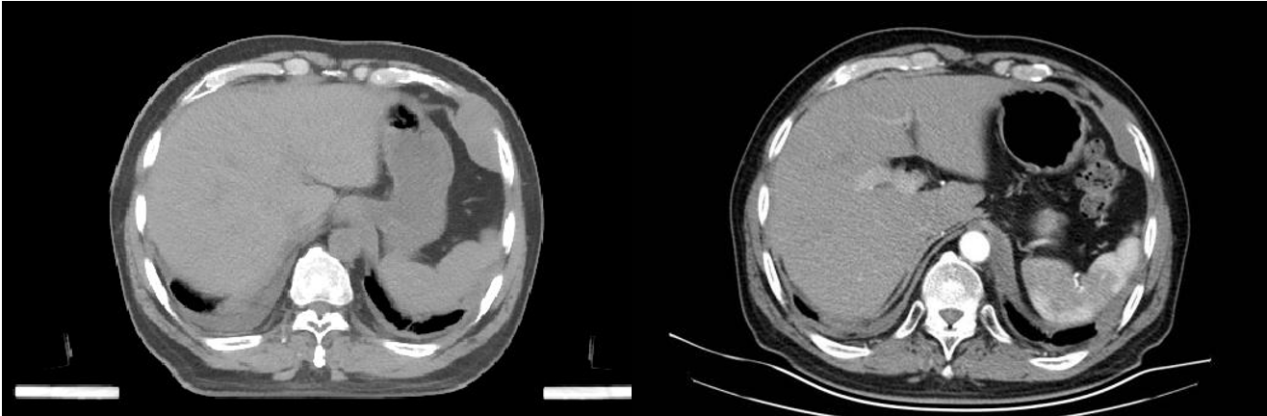

在临床效果方面,接受治疗的患者短期内骨痛即明显减轻,可逐步脱离强效止痛药,翻身、行走等日常活动能力恢复。治疗前后的CT影像对比显示,病灶及周围软组织肿物范围显著缩小,骨质破坏进展得到有效遏制,癌细胞活性明显下降。此外,该治疗方式便捷性突出,患者仅需住院2至3天即可完成治疗,全程无明显不良反应,术后无放射源残留,治疗结束当天即可恢复正常生活,且治疗费用相对较低。

患者2治疗前后图像